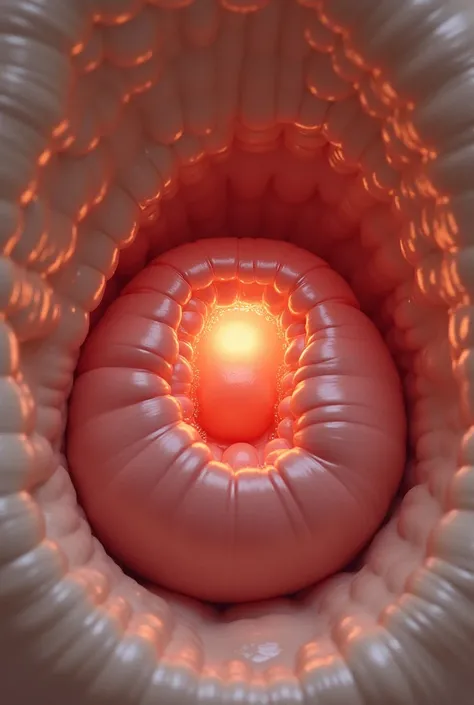

Image of a 10-week-old embryo in a uterus, captura, maternal photography 4 k

Image of a 10-week-old embryo in a uterus, captura, maternal photography 4 k, high quality scan, extremely high quality scan, high resolution scan,, video still, feto, webcam footage, high resolution scan, Escaneo profesional de alta calidad, metraje realista. hiper realista

Image of a 10-week-old embryo in a uterus